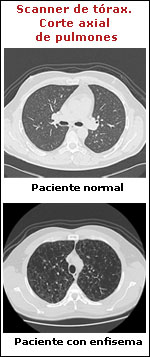

El enfisema pulmonar se manifiesta con sensación de cansancio o disnea. Consiste en un aumento permanente de los espacios aéreos responsables del intercambio gaseoso con destrucción de las paredes alveolares. El único examen que puede confirmar la existencia de enfisema es la biopsia pulmonar. Sin embargo, un scanner de tórax puede mostrarlo en una etapa temprana, con lo que se evita una biopsia. La radiografía sólo lo detecta en etapas avanzadas.